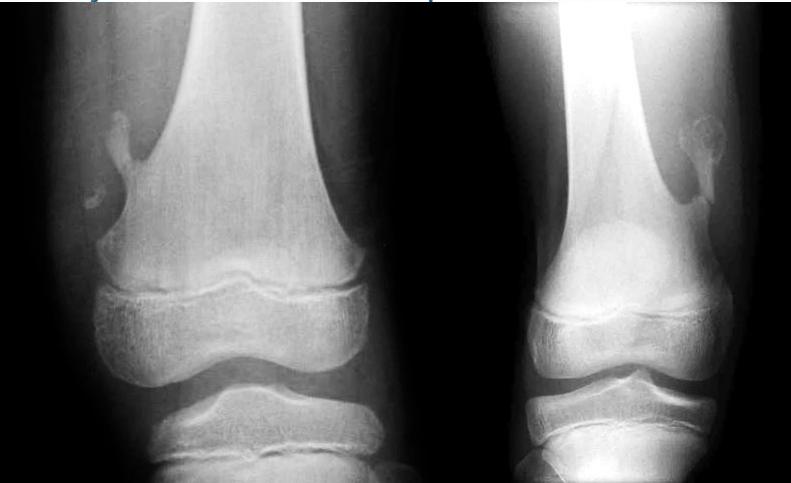

Non-Ossifying Fibroma

- Another name: Fibrous cortical defect

- The commonest benign lesion of bone

- Asymptomatic:

- Incidentally discovered

- Children:

- Disappears later

- Common site:

- Metaphysis of long bones

- Treatment:

- Observation

- Surgery if very large

Source: Apley’s System of Orthop. And Fractures

Non-ossifying fibroma …Fibrous cortical defect